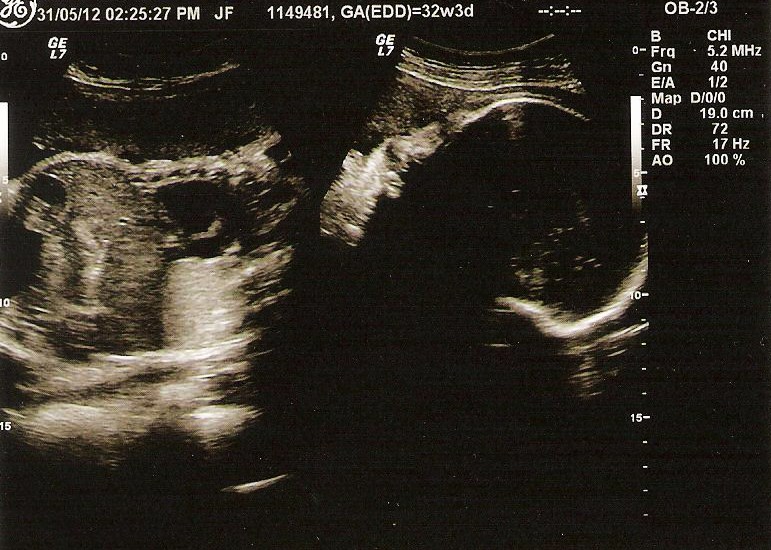

She let me see the screen finally but I couldn't really make it out. I asked for a picture but the baby is so much bigger than last time that she couldn't fit on the screen. So the technician took a couple of snaps of her head and torso and pieced them together. You really can't make it out too well...

It helped when she pointed out to me on the screen "There's the baby's face, arms, legs, heart, spine..." When I try to decipher it on my own I'm not really sure what I'm seeing. I caught a glimpse of the baby's face though, her nose, her eyes. My little girl.